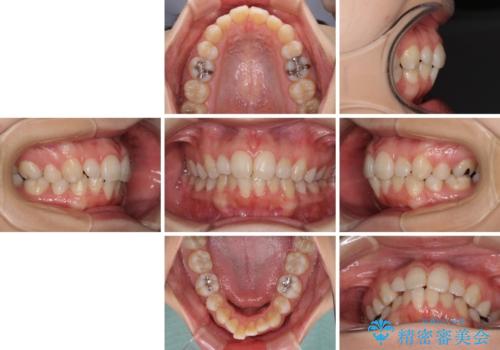

抜歯矯正の後戻り インビザライン・ライトによる矯正治療

- 矯正治療の後戻りを気にして来院された患者様です。

後戻りは軽微であったので、インビザライン・ライトにより矯正治療を行うこととしました。